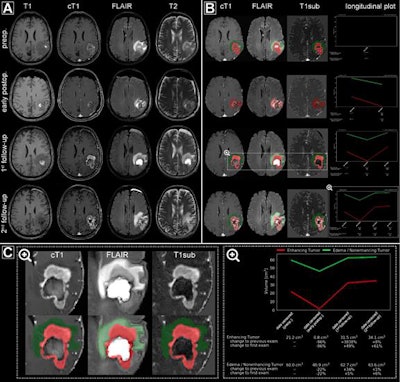

In an attempt to overcome the inherent limitations of manual tumor burden assessment, the researchers sought to develop an ANN-based framework to yield fully automated quantitative analysis. They first gathered a training dataset of MRI data from 455 nonconsecutive patients with brain tumors receiving treatment at Heidelberg University Hospital. They then trained an ANN to identify and localize the brain tumors, as well as volumetrically measure the contrast medium-absorbing tumor portion and peritumoral edema. It was also trained to precisely assess treatment response.

After validating and testing the ANN on internal image data, the researchers analyzed the algorithm's performance on an independent dataset from the European Organisation for Research and Treatment of Cancer (EORTC) 26101 trial, a prospective, randomized phase II/III trial of patients with first progression of a glioblastoma after standard chemoradiotherapy. This dataset included 532 patients with 2,034 individual MRI studies acquired from 16 different scanners at 34 institutions in Europe.

The ANN yielded excellent performance for accurately detecting and segmenting contrast-enhancing tumors (median Dice coefficient, 0.91) and nonenhancing T2-signal abnormalities (median Dice coefficient, 0.93) on the EORTC dataset. What's more, the researchers found that quantitative assessment of tumor response via the ANN (hazard ratio, 2.59) was a significantly better (p < 0.0001) surrogate end point for predicting overall survival than manual assessment based on the Response Assessment in Neuro-Oncology (RANO) working group criteria (hazard ratio, 2.07).

To assess the variability of the ANN, the researchers determined the agreement of the automated assessment versus the radiologist ground-truth assessments for quantitative volumetrically defined time to progression. For manual assessment, the researchers compared the agreement of RANO assessments performed at local institutions with RANO assessments calculated during the EORTC trial's central review process.

The ANN had 87% agreement with radiologist ground truth, a 36% margin of improvement over the 51% agreement found between local and central RANO assessments. The difference was statistically significant (p < 0.0001).

To accomplish that goal, the researchers developed and evaluated a software infrastructure that enables the integration of their method into existing radiological workflow. In testing on a simulation dataset of 466 patients with brain tumors and 595 MRI scans, the software infrastructure enabled automated on-demand processing and quantitative tumor response assessment to be completed in an average of 10 minutes per scan.